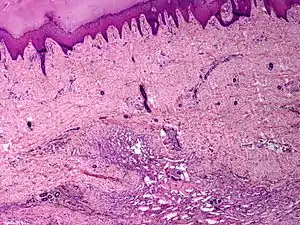

Angiomatosis is a non-neoplastic condition[1] characterised by nests of proliferating capillaries arranged in a lobular pattern, displacing adjacent muscle and fat.[2] It consists of many angiomas.[3]

These tend to be cavernous hemangiomas, which are sharply defined, sponge-like tumors composed of large, dilated, cavernous vascular spaces.

It is a vascular malformation wherein blood vessels proliferate along with accompanying mature fat and fibrous tissue, lymphatics and sometimes nerves.[2] They may involve skin, subcutaneous tissue, skeletal muscle and occasionally bone.[2]